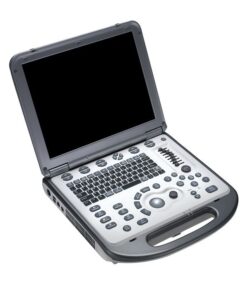

Hitachi HI VISION Avius – Diagnostic Ultrasound System

The HI VISION Avius is engineered to deliver the high-performance imaging techniques previously reserved for only the most expensive ultrasound systems. It packages many of Hitachi’s industry-leading imaging features into one affordable and mobile system.

Hitachi HI VISION Avius – Diagnostic Ultrasound System

A high performance ultrasound platform inspired by experience

The Hitachi HI VISION Avius diagnostic ultrasound is inspired by experience. Is a platform that is small in stature but big in performance. With the same performance reliability and attractive system design of the new HI VISION ultrasound platform range. You will find the Avius hard to resist.

Our new system architecture, incorporating the latest broadband beamforming technology. The ultra high-speed signal processing capability, will inspire you with confidence to put the Hitachi HI VISION Avius at the heart of your diagnostic and interventional therapeutic ultrasound practice.

Advanced Product Features

In today’s busy healthcare environment we know what a difference user-friendly equipment can make to your daily workload. You asked for a system that is easy to use and improves workflow – we have given you a simple elegant operator console and put efficient imaging parameter control at your fingertips.